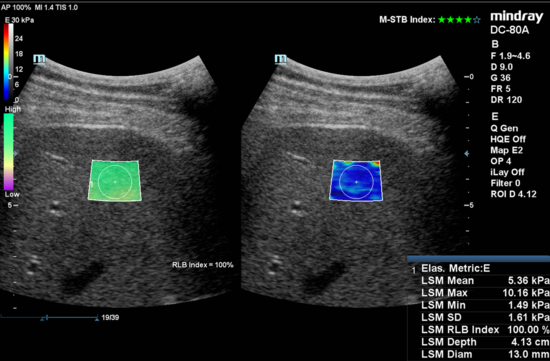

For detection and staging of fibrosis several commercial ultrasound techniques like: Transient Elestography (TE) and Shear wave elastography (SWE) are available. We currently are comparing the inter-changeability of those techniques, as well as comparing the Residual Attenuation Coefficient (RAC) from CAUS vs the Continues Attenuation Parameter (CAP) of the Fibroscan device in a large cohort of HIV patients (n=2000).

Figure 2. Example image of clinically obtained liver stiffness by using Shear Wave Elastography (Mindray Medical)